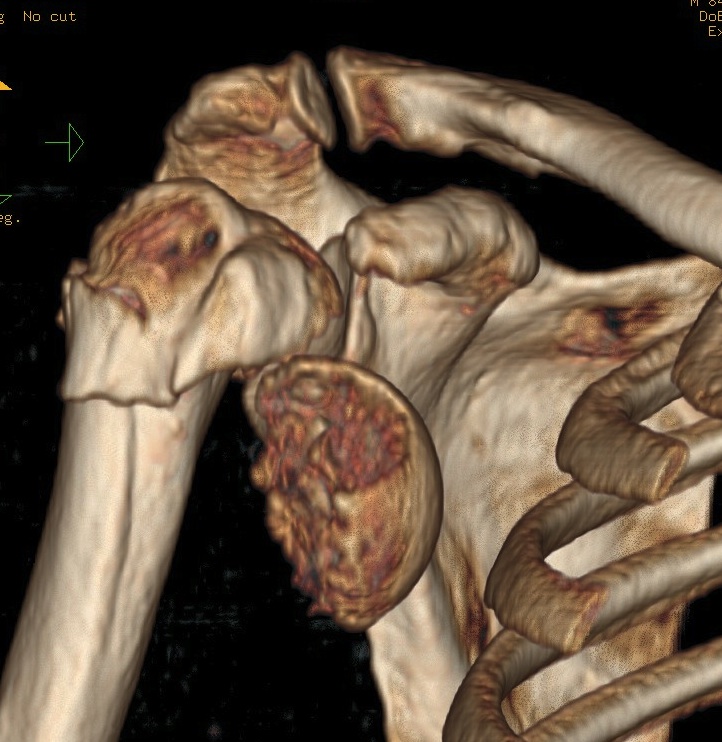

proximal humerus fracture Background ORIF with locking plate Arthroplasty Greater tuberosity fractures Lesser tuberosity fractures / avulsions Book traversal links for Proximal humerus fractures ‹ Pectoralis Major Tears Up Background ›